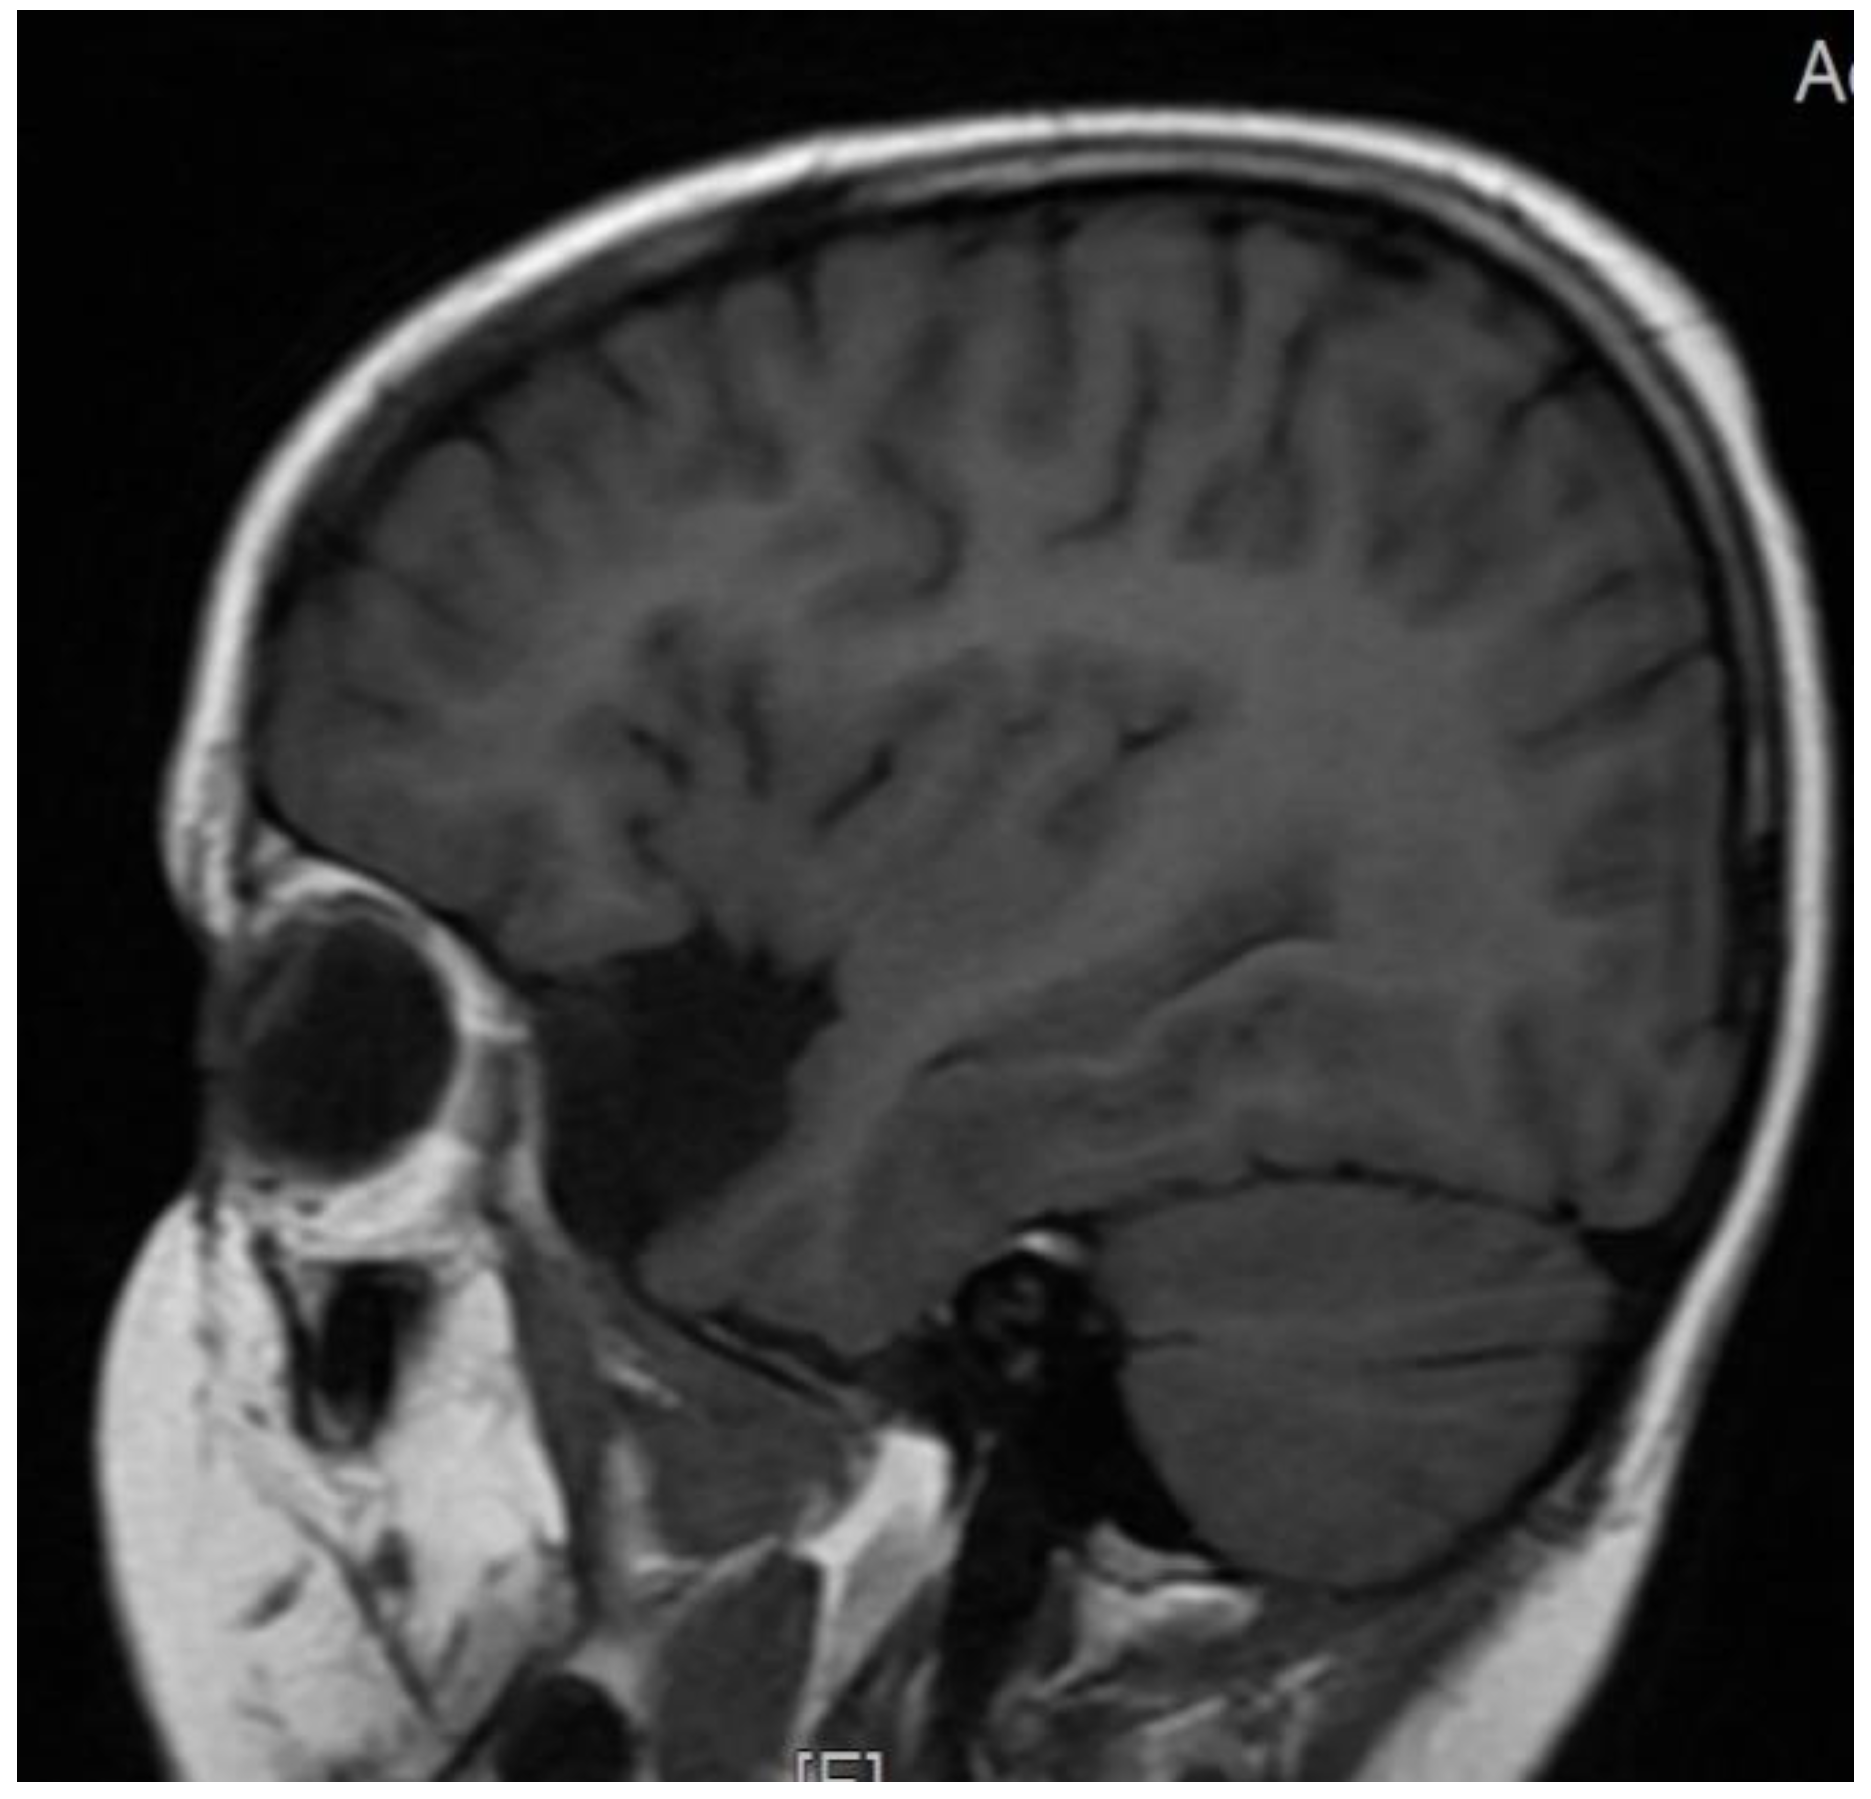

| Brain MRI | |

| yes | Changes in temporal lobe- cyst |